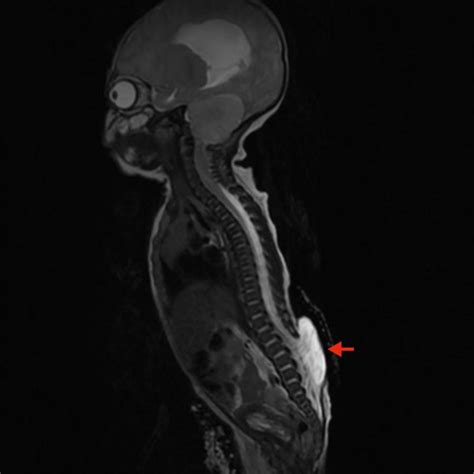

At its core, Chiari Type 2 involves the downward displacement of the cerebellar tonsils, the brainstem, and the fourth ventricle through the foramen magnum, which is the large opening at the base of the skull. This displacement creates a bottleneck effect that interferes with the normal flow of cerebrospinal fluid (CSF). Because this condition is developmental, it typically manifests in infants, as the structural abnormalities are present from birth.

The primary concern with this malformation is the obstruction of CSF circulation, which frequently leads to hydrocephalus—a condition where fluid accumulates in the brain, causing increased intracranial pressure. The structural interplay between the spine and the skull in these patients necessitates a highly coordinated medical approach involving neurosurgeons, pediatricians, and specialized therapists.

MRI (Magnetic Resonance Imaging) Provides detailed images of the cerebellum, brainstem, and spinal cord to assess the degree of herniation.